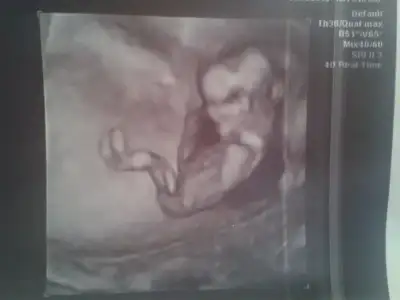

kızlarr :) 12+3 günlüğüz doktor kız dedi :) tahminler tuttu yani :) tekrar bi bakın :)

kızlar 12 haftalık...

doktor birdahakı ay bakalım yanılma çok oluyor dedi....sizce ?

ben başından beri erkek hissediyorum ama yanılabılırım

sağlıklı olsun tabı en onemlsı o.